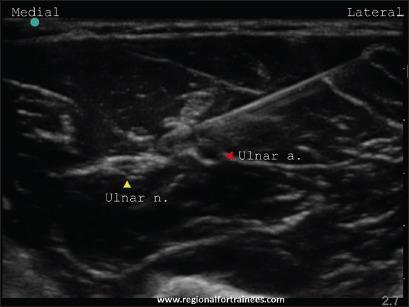

Upper extremity surgery is commonly performed under regional anesthesia. The advent of ultrasonography has made performing upper extremity nerve blocks relatively easy with a high degree of reliability. The proximal approaches to brachial plexus block such as supraclavicular plexus block, infraclavicular plexus block, or the axillary block are favored for the most surgical procedures of distal upper extremity. Ultrasound guidance has however made distal nerve blocks of the upper limb a technically feasible, safe and efficacious option. In recent years, there has thus been a resurgence of distal peripheral nerve blocks to facilitate hand and wrist surgery. In this article, we review the technical aspects of performing the distal blocks of the upper extremity and highlight some of the clinical aspects of their usage.

上肢手术通常在区域麻醉下进行。超声检查的出现使得进行上肢神经阻滞相对容易,且可靠性高。对于大多数上肢远端的外科手术,臂丛神经阻滞的近端入路,如锁骨上神经丛阻滞、锁骨下神经丛阻滞或腋路阻滞,是比较常用的。然而,超声引导使得上肢远端神经阻滞成为一种技术上可行、安全且有效的选择。近年来,远端周围神经阻滞因此再度兴起,以方便手部和腕部手术。在本文中,我们回顾了进行上肢远端阻滞的技术要点,并强调了其使用的一些临床方面。